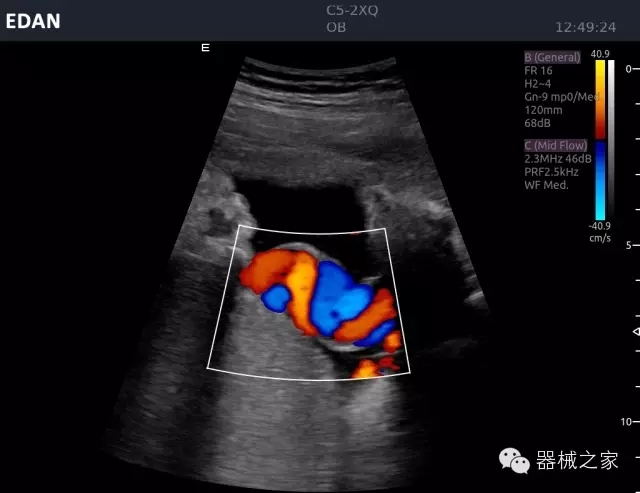

經(jīng)典產(chǎn)品:Acclarix AX8

臨床圖片賞析

睪丸低速血流

臍帶血流

頸動(dòng)脈頻譜